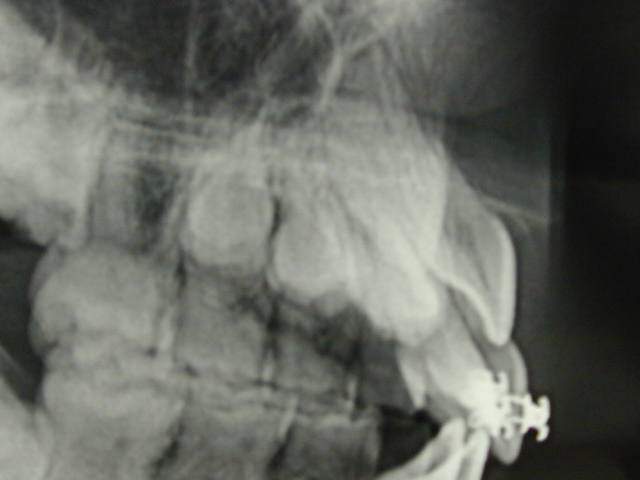

Image radio curieuse.

Lacand ayant des petits problemes de connexion internet, il m'a permis en son nom de diffuser les 3 images, qu'il vous commentera par la suite.